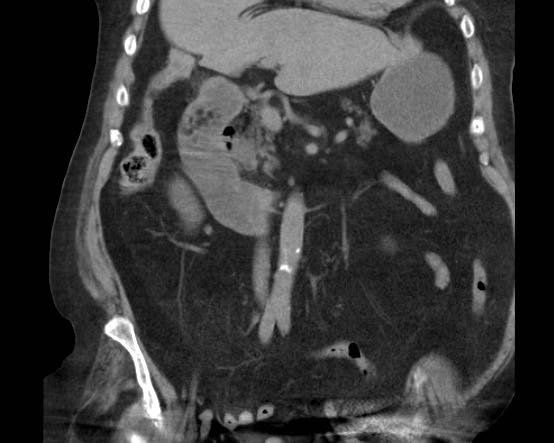

Hội chứng Bouveret

Trong các trường hợp hiếm gặp của rò tá tràng, một viên sỏi mật lớn có thể bị “kẹt” trong quá trình rò kéo dài.

Do mô viêm và mô xơ thứ phát, tình trạng này có thể dẫn đến hẹp và tắc nghẽn tá tràng.

Tình huống đặc biệt này được gọi là “hội chứng Bouveret” với biểu hiện lâm sàng chính là tắc nghẽn đường ra dạ dày (hình).

Mặc dù hiếm gặp, việc chẩn đoán chính xác là vô cùng quan trọng, vì cắt túi mật rất nguy hiểm và cần tránh thực hiện.

Nếu không thể lấy sỏi qua nội soi, giải pháp tốt nhất là phẫu thuật nối vị tràng (gastrojejunostomy).

Đây là bệnh nhân có tình trạng ứ đọng dạ dày từng đợt và CRP thấp.

Một viên sỏi lớn bị “kẹt” trong đường rò từ túi mật biến dạng đến tá tràng.

Dày thành tá tràng thứ phát (đầu mũi tên) cùng mô viêm và mô xơ xung quanh gây ra tình trạng ứ đọng dạ dày từng đợt kèm nôn mửa.